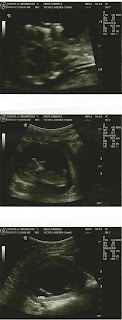

Our first peek at Baby G, whom Pat and I affectionately call "Squirmy" because of how active he or she is already (this scan was done at about 10.5 weeks). The doctor had a hard time getting decent photos because baby was moving so much. But we didn't mind one bit. That moment of seeing our baby for the first time was surreal. Indescribable. Best feeling ever.

And this is what baby looked like at 12 weeks. Reading ultrasound photos is like reading a map of a place you've never been. Unless you know exactly what landmarks you're looking for, it's a complete puzzle (or in this case, a mass of blobs in differing shades of black, white, and gray). Luckily my husband is a bit more of an analytic thinker than myself, and could help me decipher what these pictures were. In the left photos, the top picture is a profile of the baby's head. The middle one is baby with its hand up to its mouth (baby was sucking on his/her thumb almost the entire time!). And then the bottom picture, as the label would indicate, is an arm (thank you, ultrasound tech!). The picture on the right is my absolute favorite picture, and the first one I've shown to family and friends because I just think it's so dang cute. Yes, friends, that thing you see protruding from the baby's mouth is, in fact, its tongue. So much personality already!